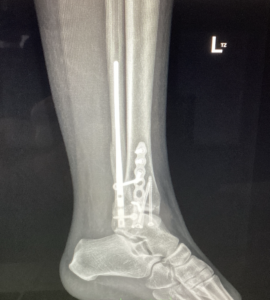

Operácia bola vykonaná 19. septembra 2025, počas ktorej bola realizovaná osteosyntéza klincom Vitus a mediálnou dlahou Arthrex, aby sa zabezpečila stabilita kostí a ich správne hojenie. Po zákroku bola končatina imobilizovaná v termoplastickej dlahe, čo je bežný postup v období bezprostredne po operácii, ktorý umožňuje ochranu operovanej oblasti a zároveň podporuje správne zhojenie kostných štruktúr.